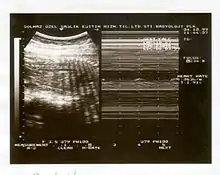

Image échographique d'une grossesse.